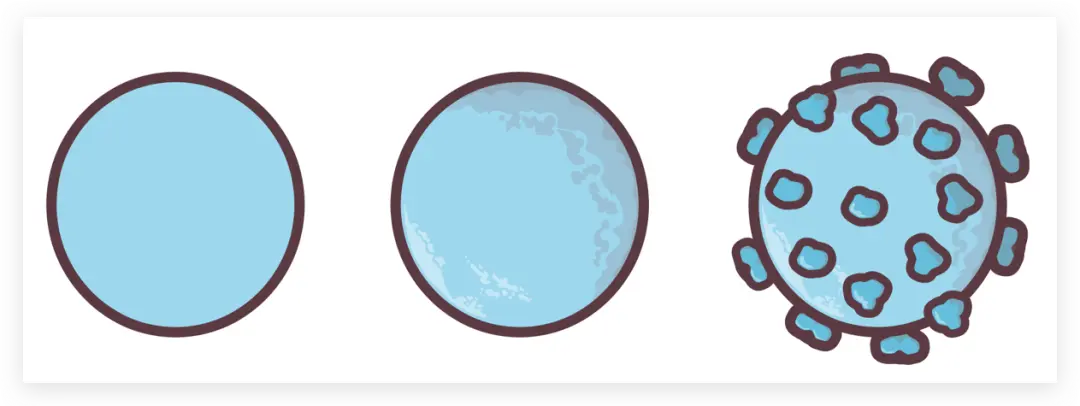

然后找到椭圆工具

画出上方四个圆

然后填充颜色

接着来画中间肿瘤细胞部分

虽然形状不同但方法一致

先用钢笔工具勾勒出外轮廓

再上色

一层层叠加图层至完成

T cells这三个形状一致,只需要把底色更换一下就可以

NK cell

Neutrophil